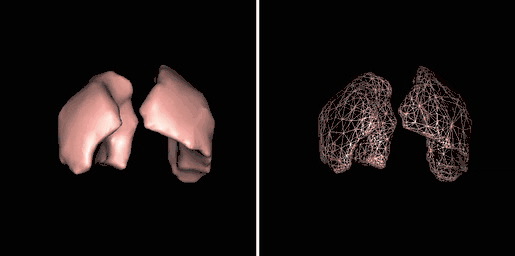

Surface Rendering

Surface rendering is also referred to as Shaded Surface Display (SSD) and involves generating surfaces from regions with similar voxel values in the 3D data as illustrated by the SPECT lung-perfusion scan shown in the left panel below:

The process involves the display of surfaces which might potentially exist within the 3D voxel data on the basis that the edges of objects can be expected to have similar voxel values. One approach is to use a grey-level thresholding technique where voxels are extracted once a threshold value is encountered in the line of the projection – see the following diagram. Triangles are then used to tesselate the extracted voxels, as shown in the right panel of the figure above – and the triangles are filled using a constant value with shading applied on the basis of simulating the effects of a fixed virtual light source – as shown in the left panel above.

An opacity table can be applied to the results so that surfaces from internal features can also be visualized. As an example, two surfaces have been identified in the following image from the CT scan where voxel values from bone surfaces are coded in an opaque yellow colour and tissue surfaces in a transparent shade of red.

A second example of using an opacity table is shown in the following figure. Here, axial CT data from the patient's airways have been segmented using a region growth technique and the result processed using surface rendering, with full opacity as shown in the left panel and with a reduced opacity (30%) as shown in the right panel:

Notice that internal features of each lung can be discerned when the opacity is reduced. Notice also that continued viewing of this type of transparency display can generate apparent reversal of the image rotation, similar to that noted for the 3D MIPs above. One method of overcoming this type of problem is to segment each lung, for instance. and to blend the results, as illustrated in the following figure: